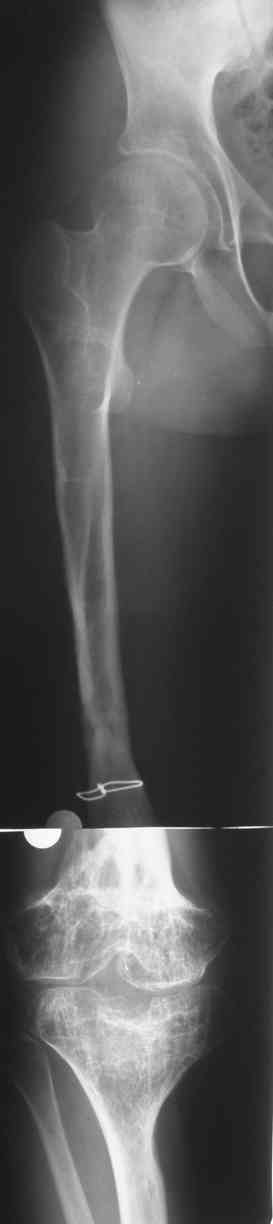

Фиброзная дисплазия бедра, укорочение 12 см.

Несколько лет нами наблюдается пациент с фиброзной дисплазией бедра (сейчас ему 18 лет).

В анамнезе 2 операции: 1.корригирующая остеотомия бедра с резекцией и аутопластикой на месте псевдоартроза бедра в н/3. 2.кортикотомия, дистракционный остеосинтез бедра в аппарате. Последний аппарат находился на больном 1г 3мес и еще 1 год ношения ортеза в связи с замедленной консолидацией.

Сейчас ортопед. укорочение конечности составляет 12 см (7 см-бедро и 5 см-голень)Движения в коленном суставе после удлинения 180-130.Удлинение бедра рикованно и грозит несращением и стойкой контрактурой колена.

Спасибо за ответы. Это рентгенограммы пациента до и после последнего удлинения бедра